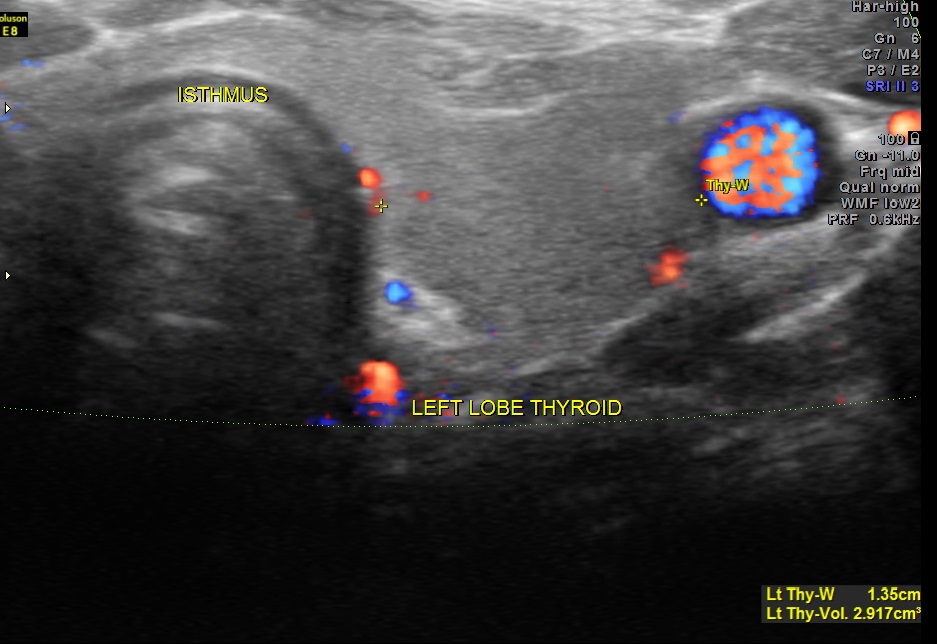

The left lobe of the thyroid and the isthmus appeared normal.

ELASTOGRAM of the mass revealed the consistency of the mass to be predominantly hard with some firm areas.